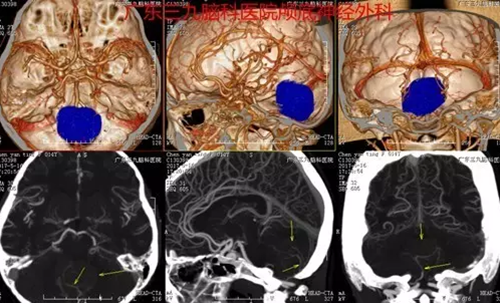

图3:术前CTA提示肿瘤血供丰富

入院后完善术前相关检查,神经外一科的专家团队为芳芳进行了“四脑室髓母细胞瘤切除术”,术程顺利,术中肿瘤全切,术后芳芳恢复良好。术后病理:髓母细胞瘤,WHO Ⅳ 级。

本例患者为13岁11月儿童,因头痛伴呕吐入院,颅内压增高症状明显,入院时MR提示病变位于四脑室底-小脑蚓部。本例患者手术过程短,术后恢复快,未有明确并发症,术后复查头颅MR提示肿瘤全切。